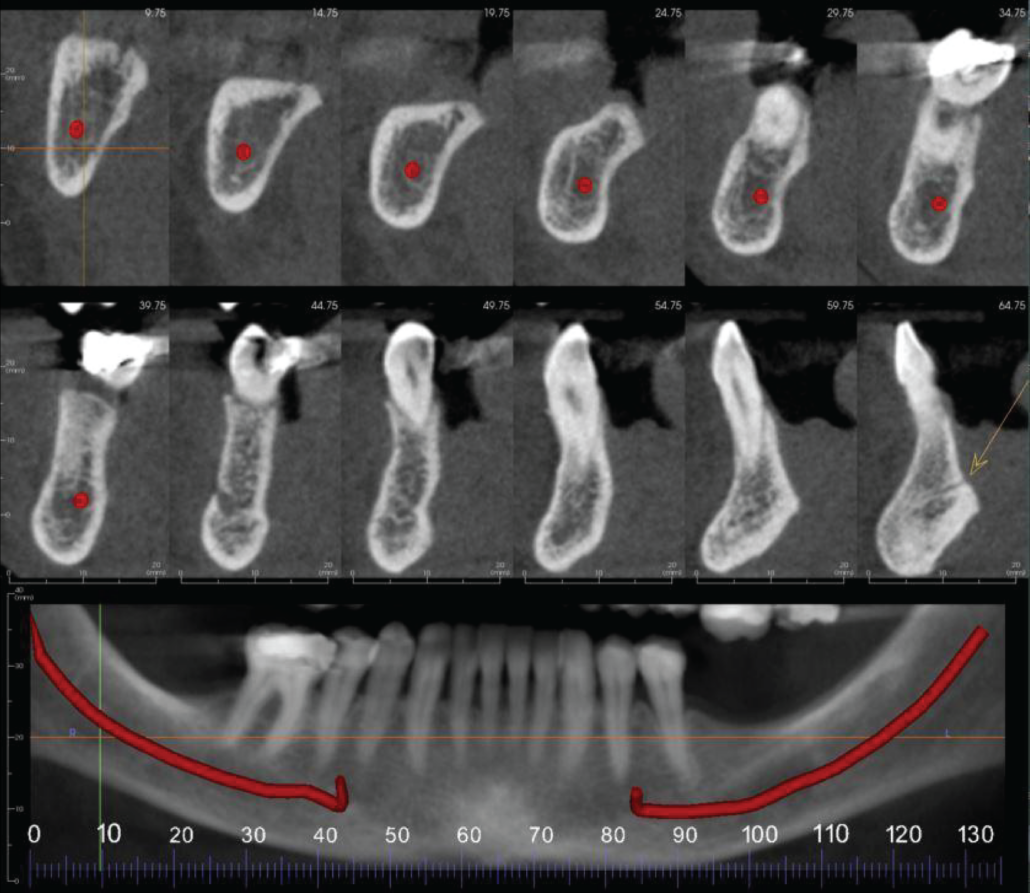

The LL7-6 region has moderate loss in vertical alveolar ridge height.

The LR7 region has moderate loss in vertical alveolar ridge height.

Cropped panoramic and cross sections of the LR8-1 region. The LR7 region has moderate loss in vertical alveolar ridge height. The midline lingual vascular canal is identified by an arrow.

Cropped panoramic and cross sections of the LL1-8 region. The LL6-7 region has moderate loss in vertical alveolar ridge height. The midline lingual vascular canal is identified by an arrow.